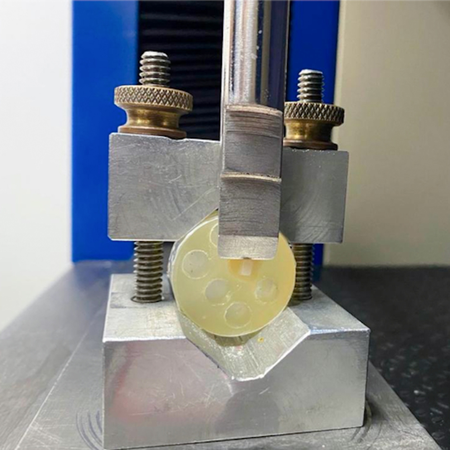

Introdução: A busca por materiais e técnicas que promovam melhor adesão ao esmalte previamente afetado por lesões cariosas tem se intensificado na Ortodontia, especialmente com o uso de resinas infiltrantes e compósitos com diferentes características. Objetivo: Avaliar a adesão de attachments ortodônticos confeccionados com diferentes compósitos em esmalte previamente infiltrado. Métodos: Noventa incisivos inferiores bovinos foram divididos aleatoriamente em 6 grupos (n=15): 1 controle Z350 (grupo C) e 5 experimentais: Z350 (grupo Z), bulk fill – 3M (grupo FM), bulk fill flow...

Introdução: A busca por materiais e técnicas que promovam melhor adesão ao esmalte previamente afetado por lesões cariosas tem se intensificado na Ortodontia, especialmente com o uso de resinas infiltrantes e compósitos com diferentes características. Objetivo: Avaliar a adesão de attachments ortodônticos confeccionados com diferentes compósitos em esmalte previamente infiltrado. Métodos: Noventa incisivos inferiores bovinos foram divididos aleatoriamente em 6 grupos (n=15): 1...

Introduction: The search for materials and techniques that promote better adhesion to enamel previously affected by carious lesions has intensified in orthodontics, especially with the use of infiltrating resins and composites with different characteristics. Objective: To evaluate the adhesion of orthodontic attachments made with different composites bonded to previously infiltrated enamel. Methods: Ninety bovine lower incisors were randomly divided into 6 groups (n=15): 1 control Z350...